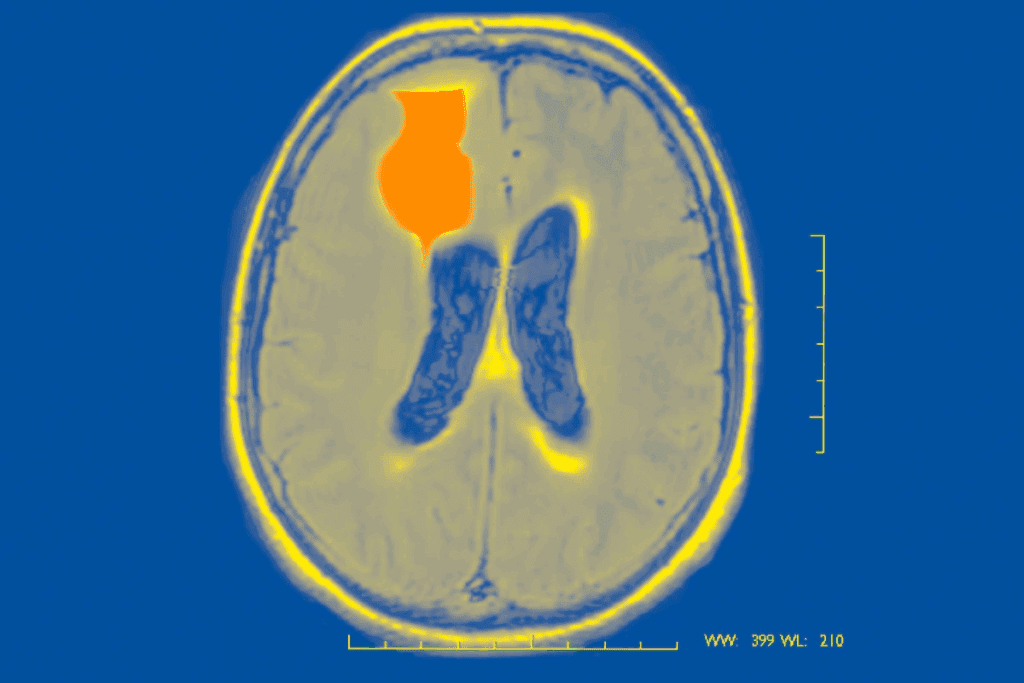

Do Seizures Cause Brain Damage? The Scientific Evidence

It’s important to know how seizures affect the brain. Research has shown both short-term and long-term effects. Seizures happen when the brain’s electrical activity goes wrong.

Many studies have looked into what happens in the brain after seizures. They found that seizures can change how the brain works and even its structure. This includes changes in electrical activity, neurotransmitters, and brain regions.